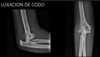

Segunda luxación más común en adultos y primera en niños

Luxación de codo

121

La luxación de codo se asocia a: | Puede condicionar:

* Fractura de coronoides * Fractura de olécranon * Lesión ligamentaria | Compromiso neural